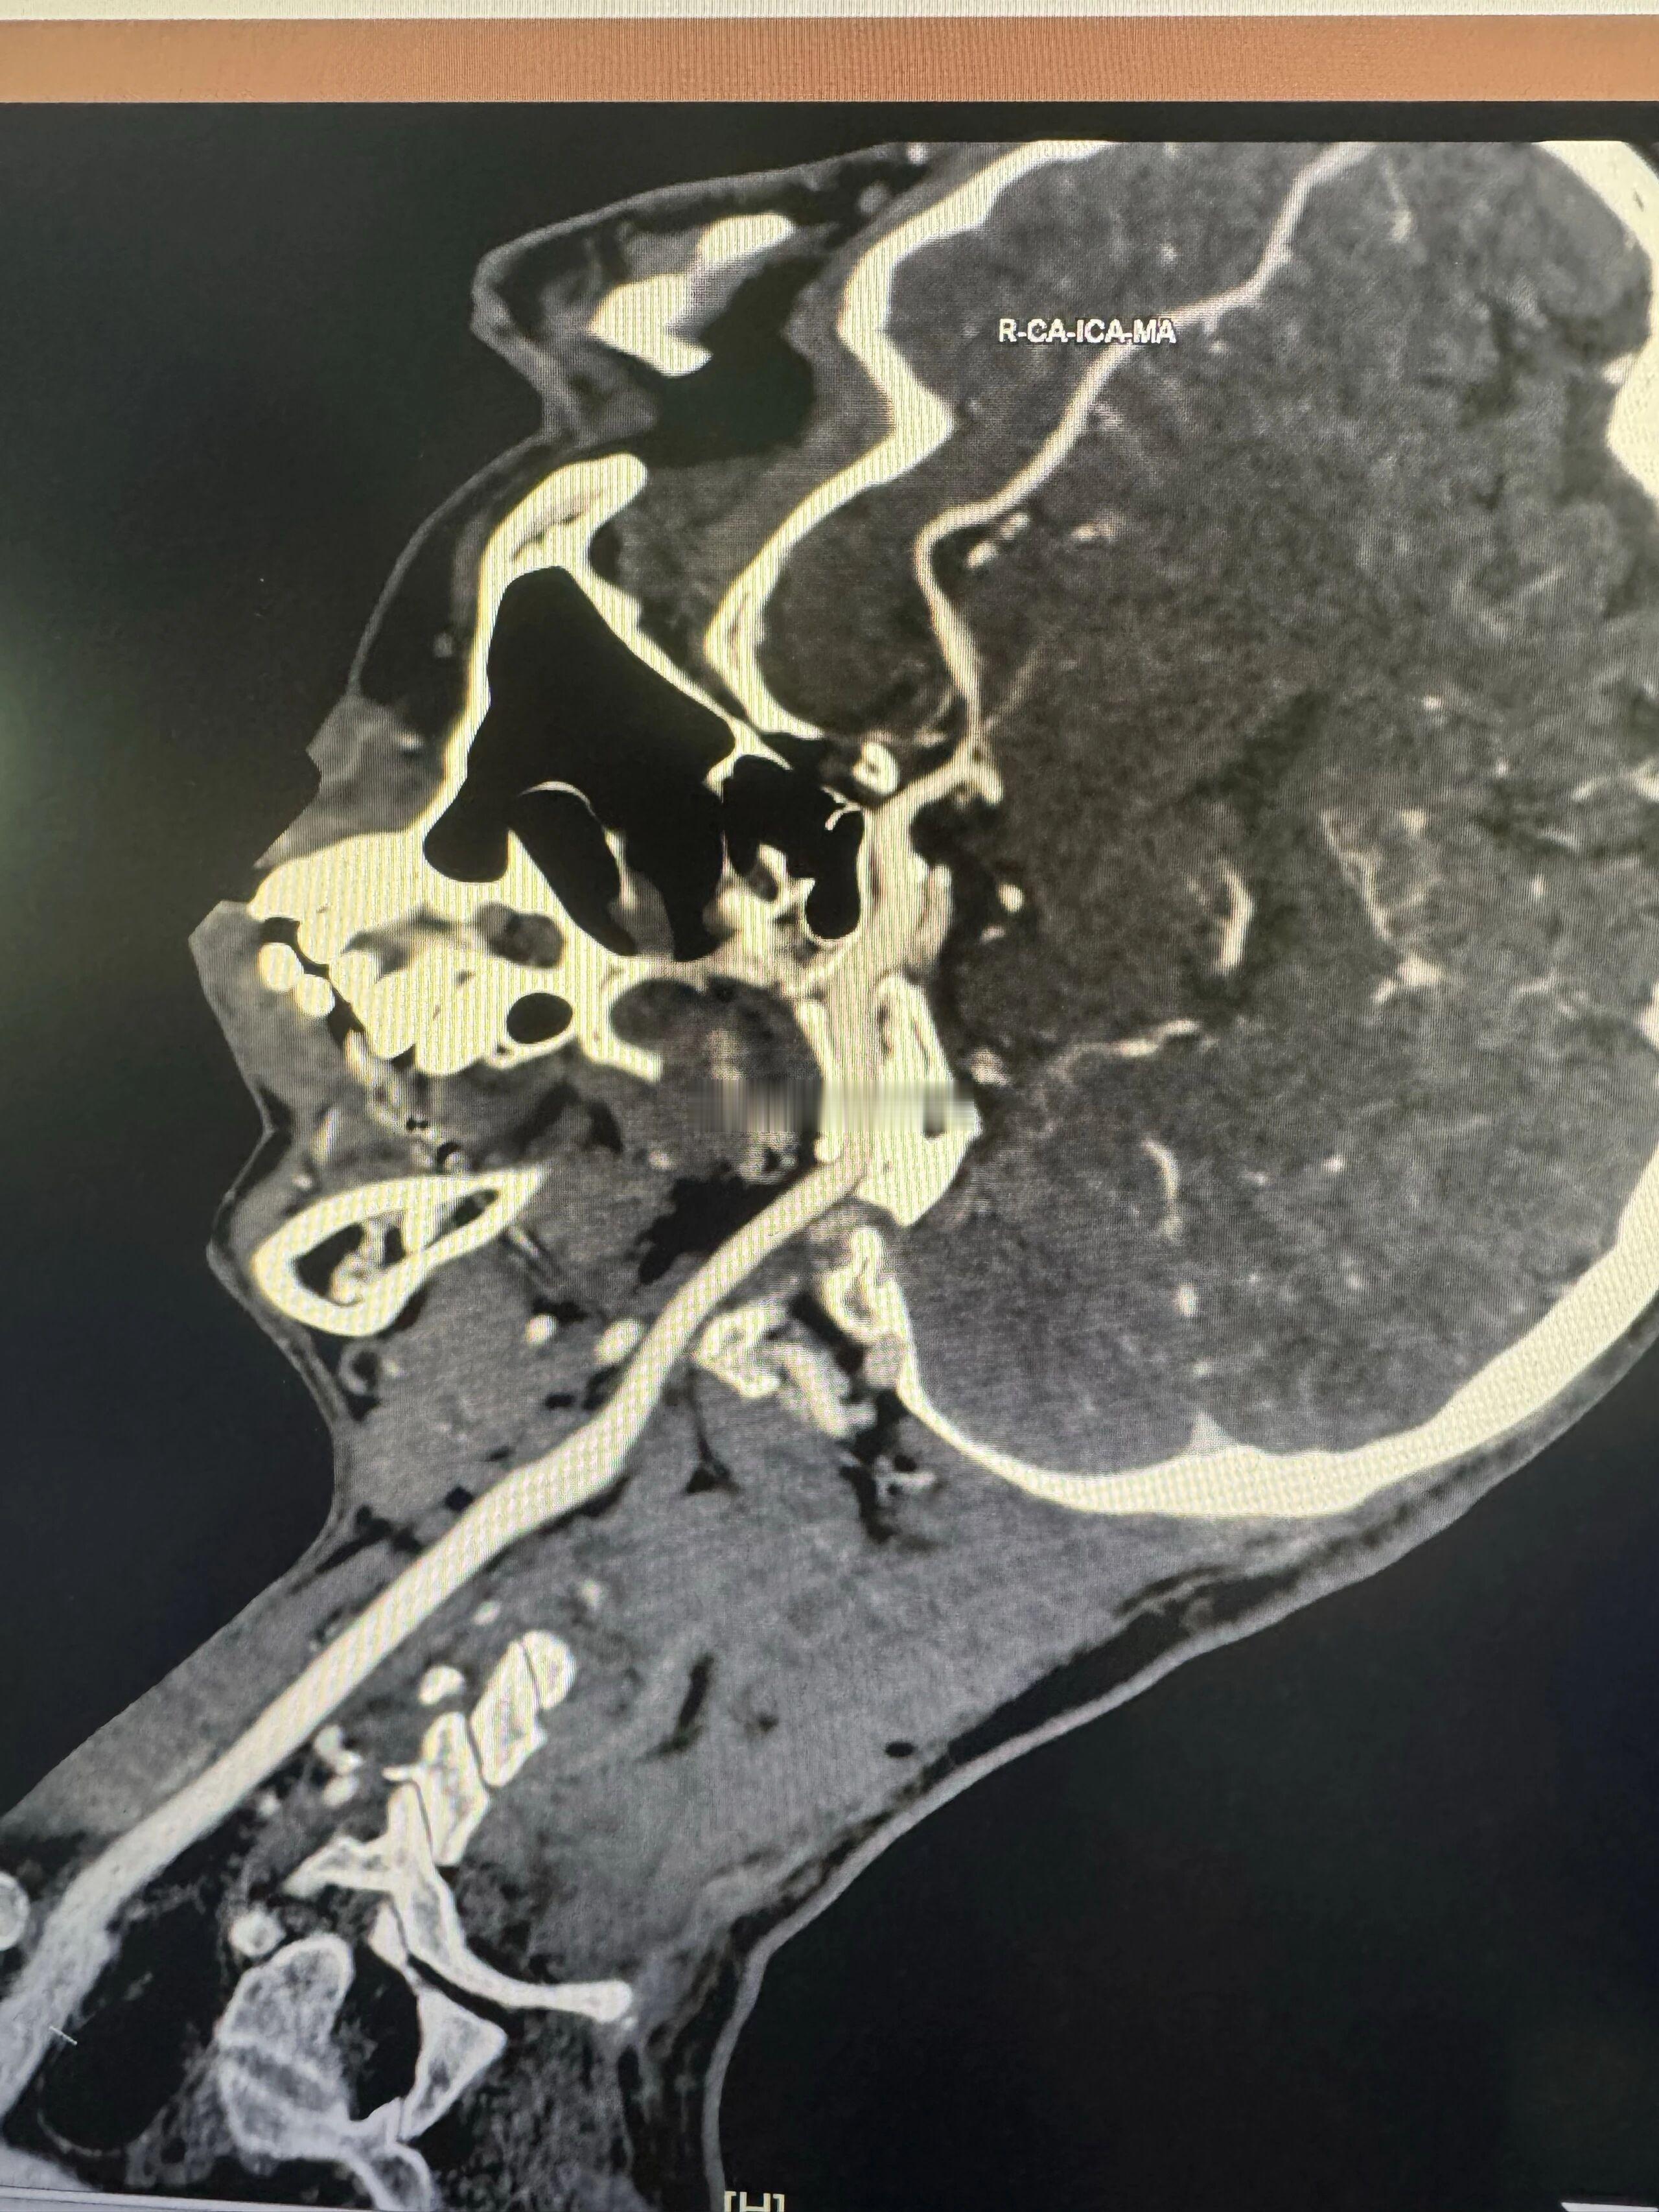

上上周跟颜老师门诊抄方,老师聊到她刚见的一位同学,谈到对手术的看法,老师这位同学大意是能解决问题的话,能不手术最好,除非万不得已,很多时候手术不是终点,后续可能还有很多事情要跟上。这个观点是很中肯的,就拿我从事的脑病来说,颅内血管重度狭窄的患者是否手术要客观评估和分析,是否可以先保守治疗后复查,看看是否有改善,而不是上来就谈手术,我们科每年有很多患者保守治疗后明显改善的,当然也有效果不理想的,比如斑块的性质,有些患者的斑块是机化钙化了的,还有个体差异等,不是说只看医生的水平。今天看到广东省中医院郭建文老师发的一个病例,右侧大脑中动脉M1段重度狭窄(图1、2),经过中西医结合治疗1年复查,基本正常了(图3、4)。